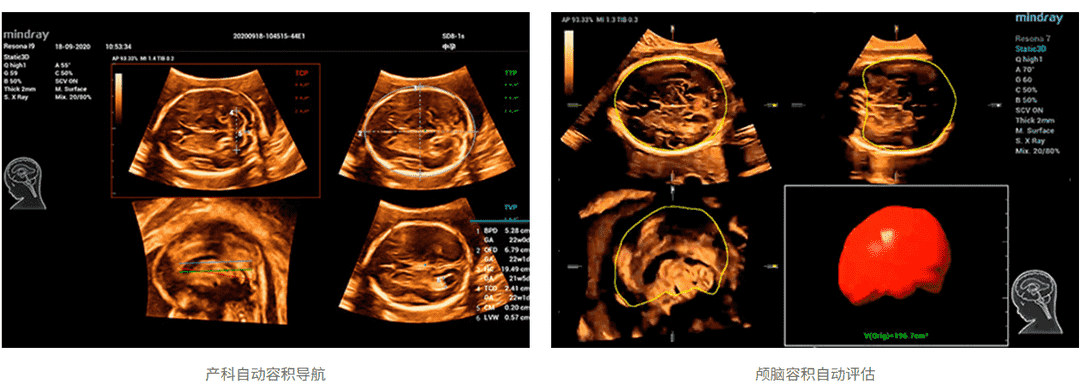

针对胎儿颅脑、面部、脊柱、长骨这类具备3D特性化的操作的临床应用场景,仁合创新开发了场景化自动容积扫描,只需“一键”即可完成自动场景识别、自动成像及优化、自动切面获取、自动定量分析,真正实现了贯穿整个检查流程的自动化工作流,降低诊断对操作者的依赖性,轻松提升病人检查效率。